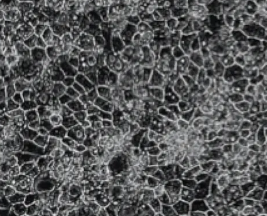

- Highly standardized with > 98% functionally mature human hepatocytes

With the ability to reliably generate functionally mature human hepatocytes from iPSCs, DefiniGEN brings all the advantages of iPSC technology to hepatocyte studies - cell models that possess human-relevant physiology and that are available in virtually unlimited amounts with the same genetic background.

DefiniGEN's human hepatocytes remain functionally stable over a prolonged period of time in culture, making them ideal for drug discovery, drug metabolism, and toxicology-related studies. They also express key hepatitis markers such as CD81, SR-B1, Claudin-1 and Occludin at similar levels to primary human hepatocytes, making them an effective model for hepatitis lifecycle studies.